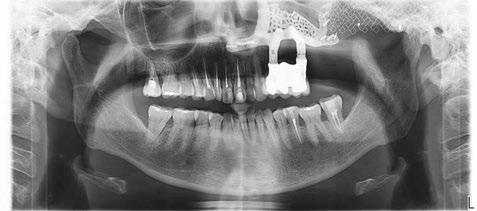

-Estudio radiográfico inicial (ortopantomografía y radiografías periapicales) (Figura 2).

Figura 2. Ortopantomografía inicial.